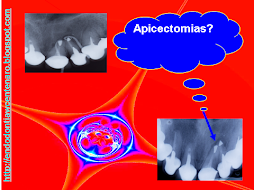

ENDO-OCLUSÃO

A ENDODONTIA PODE FRACASSAR SE A OCLUSÃO TIVER AJUSTADA

PELO DESGASTE APRESENTADO DA PARA IMAGINAR O QUE VAI ACONTECER!!!

SERÁ?

DOR!!!!!!!!!!!!!!!!!

É DA ENDO?

TINHA QUE DAR NISTO!!!!

E AGORA?